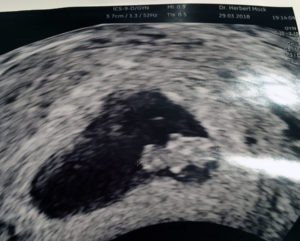

It is still very early with my second pregnancy, week 8 only, however we are hoping for the best. THANK You all at A Personal Choice !!!!!!!

I did not find the possibility to post a picture here, therefore I have sent one to the messenger inbox of Dr Monteith.